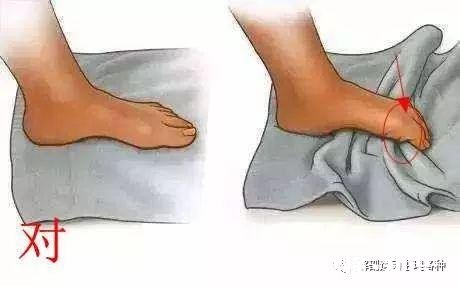

6.抓毛巾

一般网上能查到的都是让你抓毛巾,你们也就用脚趾开始了训练,但是发现了吗,你们都是用脚趾前面部分用力抓毛巾,而不是用脚趾根部的位置 。

正确的方式是用脚趾根部的位置 。